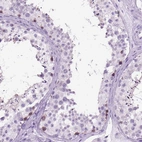

Immunohistochemistry analysis in human testis and endometrium tissues using Anti-HHIPL2 antibody. Corresponding HHIPL2 RNA-seq data are presented for the same tissues.